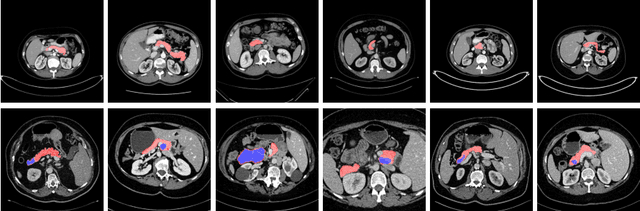

Abstract:Deep learning algorithms, in particular 2D and 3D fully convolutional neural networks (FCNs), have rapidly become the mainstream methodology for volumetric medical image segmentation. However, 2D convolutions cannot fully leverage the rich spatial information along the third axis, while 3D convolutions suffer from the demanding computation and high GPU memory consumption. In this paper, we propose to automatically search the network architecture tailoring to volumetric medical image segmentation problem. Concretely, we formulate the structure learning as differentiable neural architecture search, and let the network itself choose between 2D, 3D or Pseudo-3D (P3D) convolutions at each layer. We evaluate our method on 3 public datasets, i.e., the NIH Pancreas dataset, the Lung and Pancreas dataset from the Medical Segmentation Decathlon (MSD) Challenge. Our method, named V-NAS, consistently outperforms other state-of-the-arts on the segmentation task of both normal organ (NIH Pancreas) and abnormal organs (MSD Lung tumors and MSD Pancreas tumors), which shows the power of chosen architecture. Moreover, the searched architecture on one dataset can be well generalized to other datasets, which demonstrates the robustness and practical use of our proposed method.